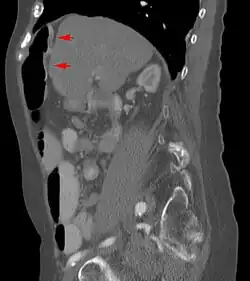

Das Chilaiditisyndrom oder Chilaiditi-Syndrom beschreibt in der Medizin eine Verlagerung und Drehung von Dick- und seltener Dünndarmanteilen von weiter fußwärts nach kopfwärts (kranial) zwischen Zwerchfell und Leber. Normalerweise findet sich in diesem Bereich kein Darm. Das Syndrom ist eine Normvariante und nicht notwendigerweise von Krankheitswert.

Das Syndrom ist eher selten (unter 1 %) und wird meist als Zufallsbefund auf Röntgenaufnahmen der Lunge, im Computertomogramm des Oberbauches oder im abdominellen Ultraschall erkannt. Bei Eingriffen an der Leber, insbesondere bei Leberpunktionen, ist die Kenntnis dieser anatomischen Variante von großer Wichtigkeit.

Es sind Anteile des Dickdarms – vor allem seine rechte obere Biegung (die Flexur) – oder seltener des Dünndarms zwischen den rechten Leberlappen und das rechte Zwerchfell verlagert. Das Syndrom kann mit Fehlbildungen der Leber, des Zwerchfells oder Dickdarmes einhergehen.

- learningradiology.com CT-Bild des Syndroms